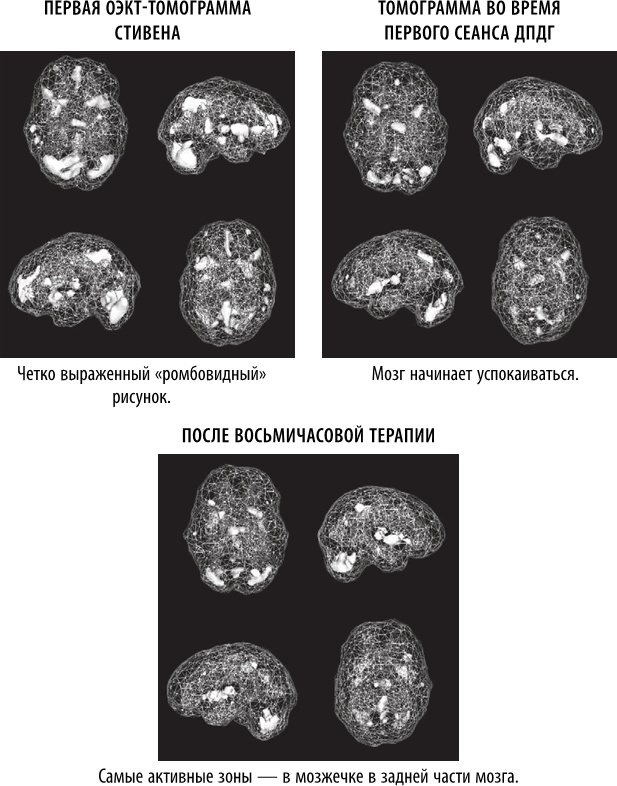

Когда продюсер CBS Анжелина Чу обратилась ко мне с вопросом, интересует ли меня телевизионный сюжет о ДПДГ с использованием истории Стивена в качестве примера, я был рад помочь. Мы с терапевтом Карен Лэнсинг только что закончили исследование о сотрудниках полиции, которые участвовали в перестрелках и в результате страдали от ПТСР [180]. Терапия ДПДГ показала свою эффективность, быстро сгладив симптомы расстройства и нормализовав мозговую функцию на ОЭКТ-томограммах. Мы с коллегами опубликовали несколько исследований о ПТСР с результатами томографии, демонстрировавшими значительный рост активности в лимбической (эмоциональной) области, образующий рисунок в форме ромба. Среди пораженных участков мозга находится передняя поясная извилина, что подразумевает фиксацию на негативных мыслях и реакциях, а также базальные ядра и миндалевидное тело, связанные с ощущением тревоги, и таламус, что указывает на повышенную сенсорную чувствительность. Кроме того, мы видели повышенную активность в правой латеральной части височной доли – области мозга, связанной с интерпретацией намерений других людей.

В ходе эксперимента мы трижды просканировали мозг Стивена: до терапии, во время первого сеанса ДПДГ и после восьми часов лечения. Сначала мозг Стивена демонстрировал классические симптомы ПТСР с крайне высокой активностью лимбической (эмоциональной) системы мозга. С помощью ДПДГ мы начали поочередно «очищать» психические травмы. Уже после первого сеанса появились признаки улучшения, а после восьми часов терапии (см. изображения выше) общая картина значительно улучшилась. У Стивена прекратилась неконтролируемая дрожь, он стал более спокойным и менее напряженным. Одним из самых поразительных эффектов терапии, которым Стивен поделился со мной, было то, что он постепенно начал прощать своего отца и думать о том, как выглядел отцовский мозг. Стивен питал глубокое и понятное отвращение к отцу, но нейронаука позволила ему посмотреть на себя и своего отца с новой стороны. Когда мы помогли Стивену успокоить и уравновесить его мозг, он стал более жизнерадостным человеком и смог лучше спать.